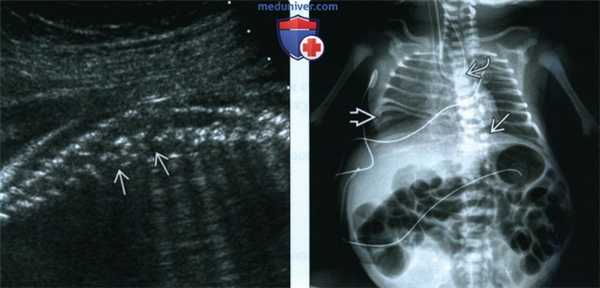

(Слева) На врезке - нормальная анальная ямка с гипоэхогенной мышечной стенкой, окружающей гиперэхогенную слизистую оболочку. Сравните со случаем отсутствия ямки у плода с атрезией ануса.

(Слева) Тот же плод. УЗИ позвоночника, сагиттальная плоскость. «Перемешанные» позвонки выглядят так из-за множественных дефектов сегментации позвонков. Полупозвонки - наиболее распространенные аномалии позвоночника при ассоциации VATER/VACTERL.

(Справа) Рентгенограмма новорожденного с ассоциацией VACTERL с орога-стральной трубкой, изогнутой в месте АП. Дистальный отдел трахеопищеводного свища отвечает за наличие газа в кишечнике. Аномалии позвонков и расширенные петли кишечника из-за атрезии анального отверстия. Также видны аномалии ребер.